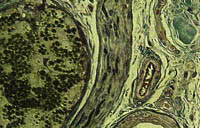

Color High-Resolution (2.5 micron) Plastic Sections Utilizing Basic Fuchsin and Methylene Blue as a Hematoxylin & Eosin (H & E) Like Stain and Trichrome-Like Stain

This colorful plastic section technique allows the investigator to examine large tissue blocks (1.0 x 1.0 x 0.2 cm) which are processed and embedded in Spurr epoxy resin for 2.5 um plastic sectioning using a JB-4 microtome. The sections are attached to glass slides and stained sequentially with methylene blue and basic fuchsin and coverslipped. The result is a brilliant H & E-like staining of the nuclear and cytoplasmic elements with a Trichrome-like stain. Listed below are the various cellular components in tissues that can be identified by this unique plastic section staining technique. Specific areas or cells can also be "popped off" these stained sections for ultrastructural examination.

| Cellular Component | Stain Color | Cellular Component | Stain Color | |

|---|---|---|---|---|

| collagen | turquoise blue | elastin | brilliant red-purple | |

| glycogen | blue | lipid | olive green | |

| myelin | dark purple | intestinal mucin | pink to purple | |

| gastric mucin | gray purple | mast cell granules | purple | |

| lipofuscin | green-black | melanin | mahogany | |

| basement membrane | pink |